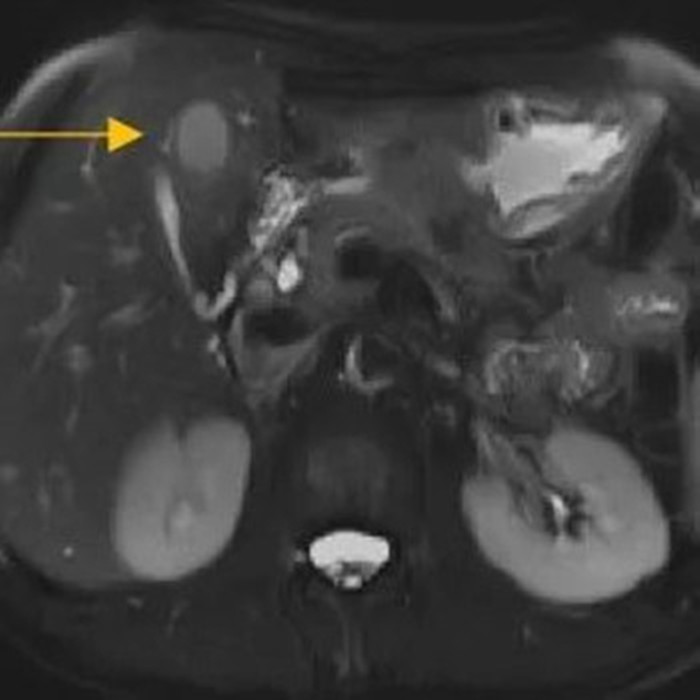

住院后經(jīng)胸腹部CT檢查,提示周先生胃部巨大腫塊穿破胃腔,可能累及到結(jié)腸,同時(shí)合并有胃旁淋巴結(jié)轉(zhuǎn)移、肝臟的轉(zhuǎn)移??吹竭@個(gè)檢查報(bào)告后,周先生和他的愛(ài)人一下子就泣不成聲了。

治療前肝臟的轉(zhuǎn)移灶

經(jīng)過(guò)6個(gè)周期,前后4個(gè)月的治療,周先生再次復(fù)查CT,提示胃部腫瘤,轉(zhuǎn)移的胃旁淋巴結(jié)、肝臟腫瘤都有明顯縮小,營(yíng)養(yǎng)狀況良好,能正常進(jìn)食,體重增加了6斤,精神狀態(tài)比原先好了很多。

治療前

治療后